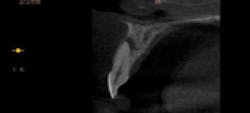

Figures 4–8: Apical lesion on tooth No. 9 is confirmed on all 3-D views

I examined a patient who had experienced trauma to his two front teeth approximately five years prior and was now experiencing occasional pain. From an x-ray, the problem could not be diagnosed as definitive (figure 3). However, as soon as I took the 3-D image, I could see an abscess, which required a root canal (figures 4–8).